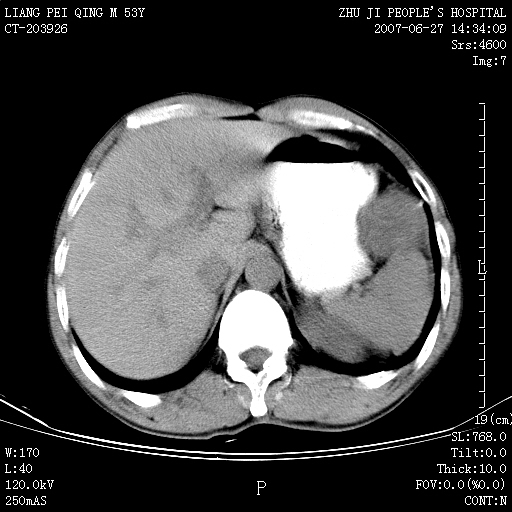

以下是引用余辉在2007-6-27 18:46:00的发言:[br]病灶多发,内可见大片状低密度区,病灶病灶等密度区轻度强化,动脉期后期病灶低密度区与高密度区对度增加,考虑1淋巴瘤2转移瘤3血管内皮细胞瘤(不知有否静脉期及延迟期扫描)

以下是引用zzzzhhhhaaaannnn在2007-6-27 20:44:00的发言:[br]脾脏 肋骨转移可能性大,下腔静脉内有癌栓

以下是引用狙击手在2007-6-28 10:35:00的发言:[br]1:定位:来源于脾脏。2:强化:强化,但不均匀。3:下腔静脉癌栓?下腔静脉充填不均匀与增强时间有关,延时即可明确。4:肋骨破坏?看起来并不确切。综上考虑几个最常见诊断:1;淋巴管瘤;2;血管内皮肉瘤(高度恶性,早期即可转移,常见肝,肺,骨)3;转移瘤(无特征性,只有肝或其它腹腔脏器有类似病变时,才可提示之)